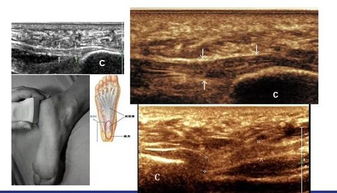

超声检查骨骼系统,就像给骨骼做了一次“透视”。医生可以通过超声图像,清晰地看到骨骼的结构、形态和密度,以及周围软组织的情况。这样一来,医生就能准确地判断骨骼系统是否存在骨折、肿瘤、炎症等问题。

当然,超声不仅仅可以检查骨骼,它还能检查肌肉、肌腱、韧带等软组织。这种专门用于检查肌肉骨骼系统的超声技术,就叫做肌骨超声。

肌骨超声在临床上有广泛的应用,以下是一些常见的应用场景:

1. 肌肉、肌腱、韧带的损伤:如肩袖损伤、跟腱断裂、肌腱炎等。